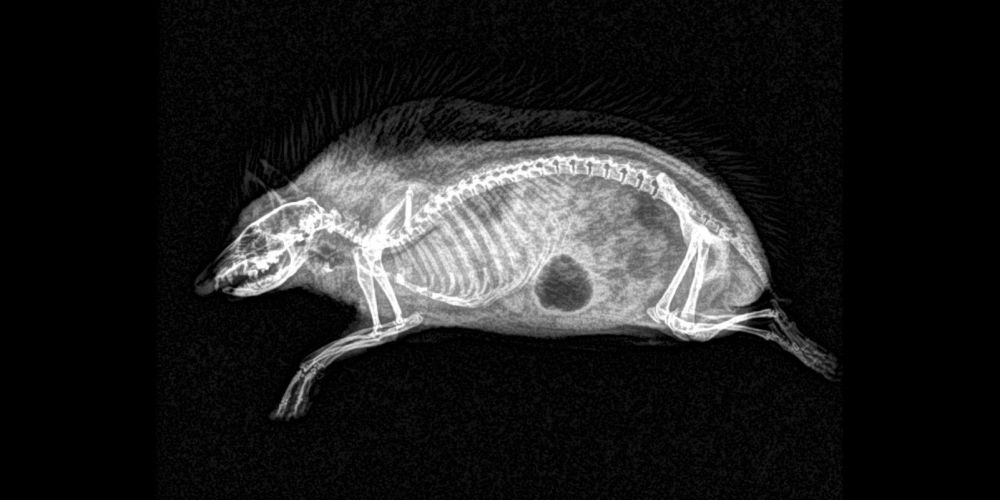

ABD'nin Oregon eyaletinde bulunan bir hayvanat bahçesi, hayvanların rutin sağlık kontrolleri sırasında çekilen X-Ray görüntülerini paylaştı.

Sağlık kontrolleri sırasında bazı hayvanlara röntgen çektiklerini söyleyen hayvanat bahçesi yetkilileri, bu yöntem sayesinde sağlık değerlendirmelerinin daha kolay yapıldığını ifade etti.